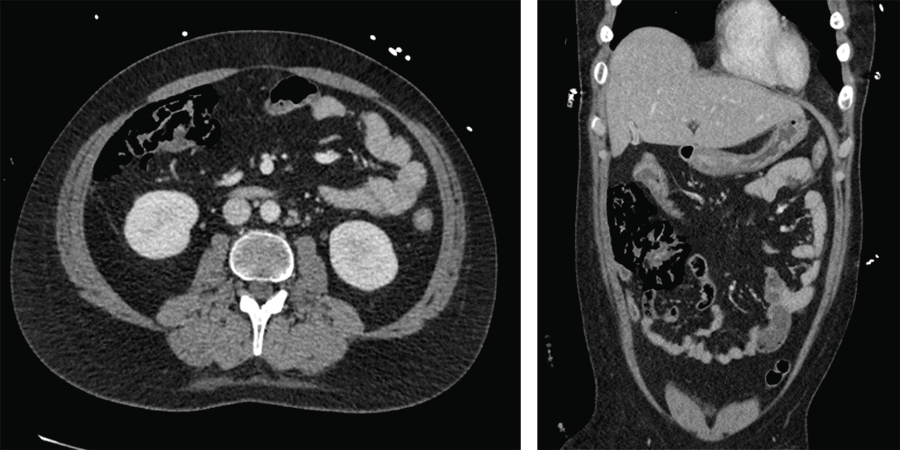

At our hospital, he received treatment with CYVE chemotherapy (cytarabine and etoposide), complicated by neutropenia and several days of diarrhea with associated abdominal pain. On day nine of treatment, he was diagnosed with Clostridium difficile (C. difficile) infection and was started on oral vancomycin. The following day, his abdominal pain acutely worsened, and he became hemodynamically unstable, requiring intubation and maximum vasopressor support. That day, his white blood cell count was 10 cells/mm3 and his platelets were 17,000 cells/mm3. Hemoglobin was 7.6 g/dL. An abdominal computed tomography (CT) scan (Figure 1) revealed pneumatosis of the right colon with extraluminal free air of the colonic mesentery suggestive of bowel perforation secondary to ischemia. He was transfused several units of platelets and packed red blood cells. Colorectal surgery was consulted, and the patient was taken to the operating room emergently for exploratory laparotomy.

Figure 1. CT Images. Published with Permission

There is extensive new pneumatosis within the wall of ascending colon with evidence of extraluminal gas contained within adjacent mesentery. Remainder of colon is thick-walled but decompressed